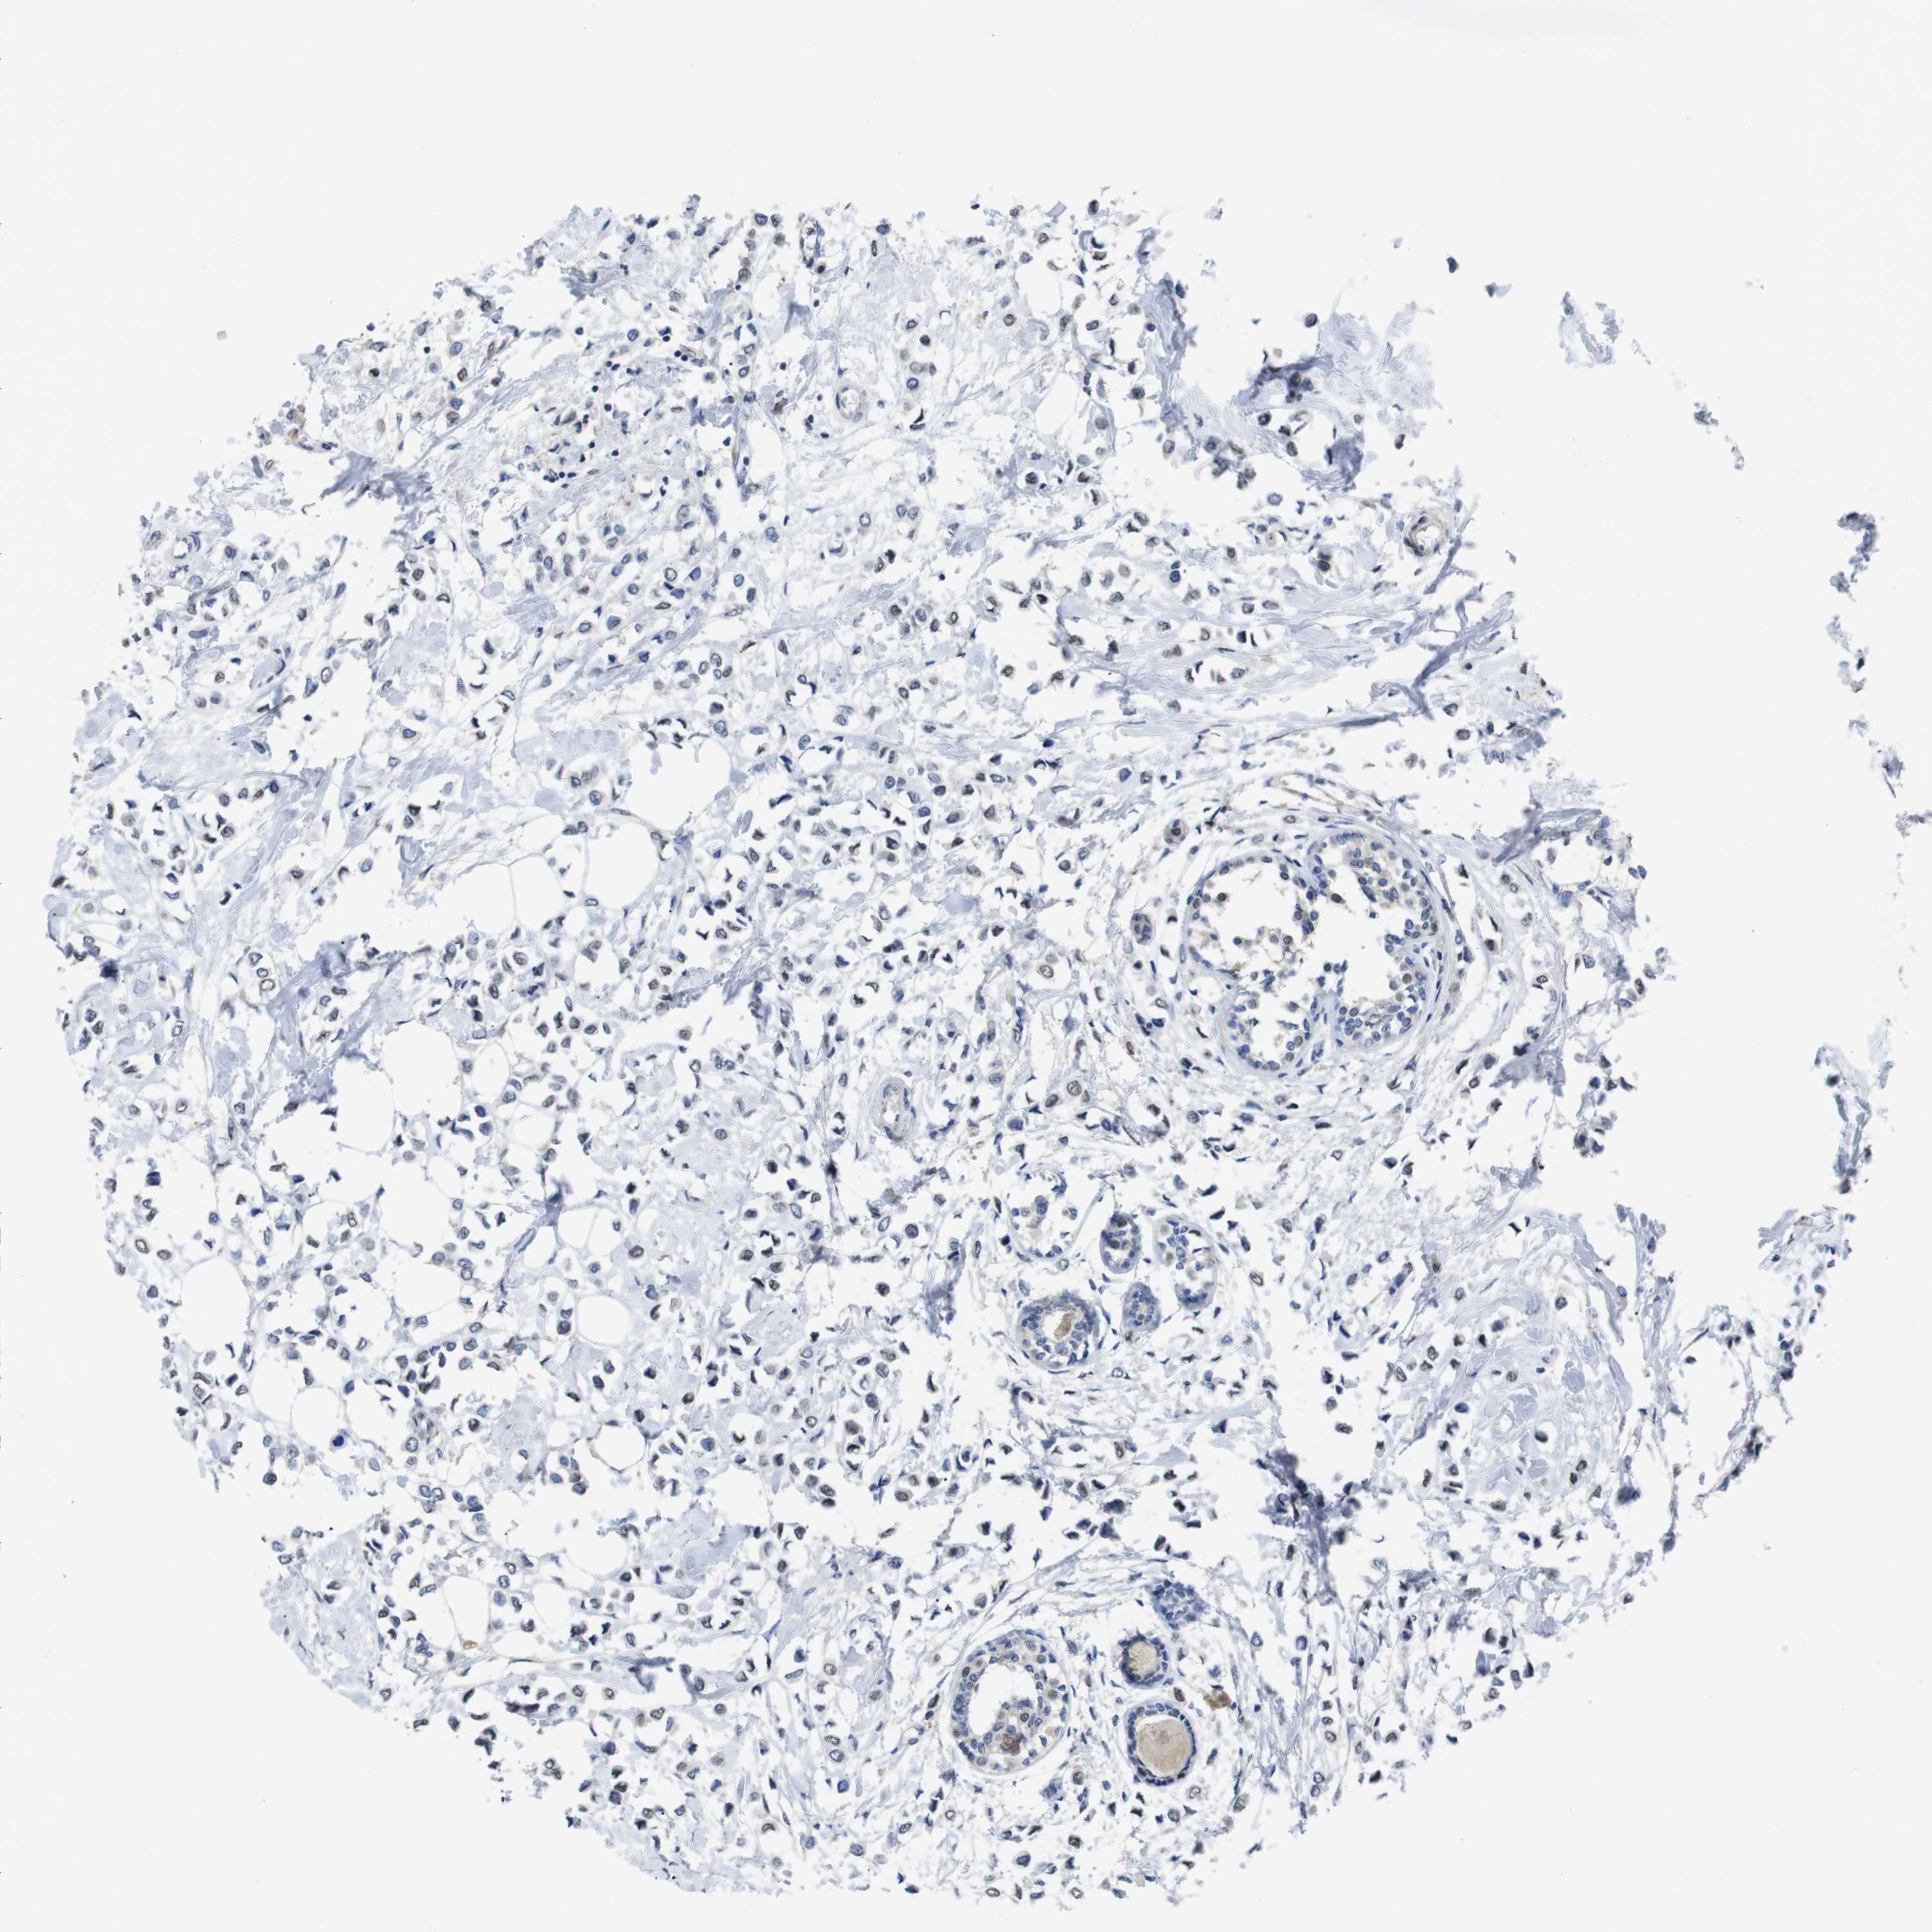

CANCER BREAST CANCER Show tissue menu

BRCA TCGA BRCA VALIDATION PROTEIN EXPRESSION